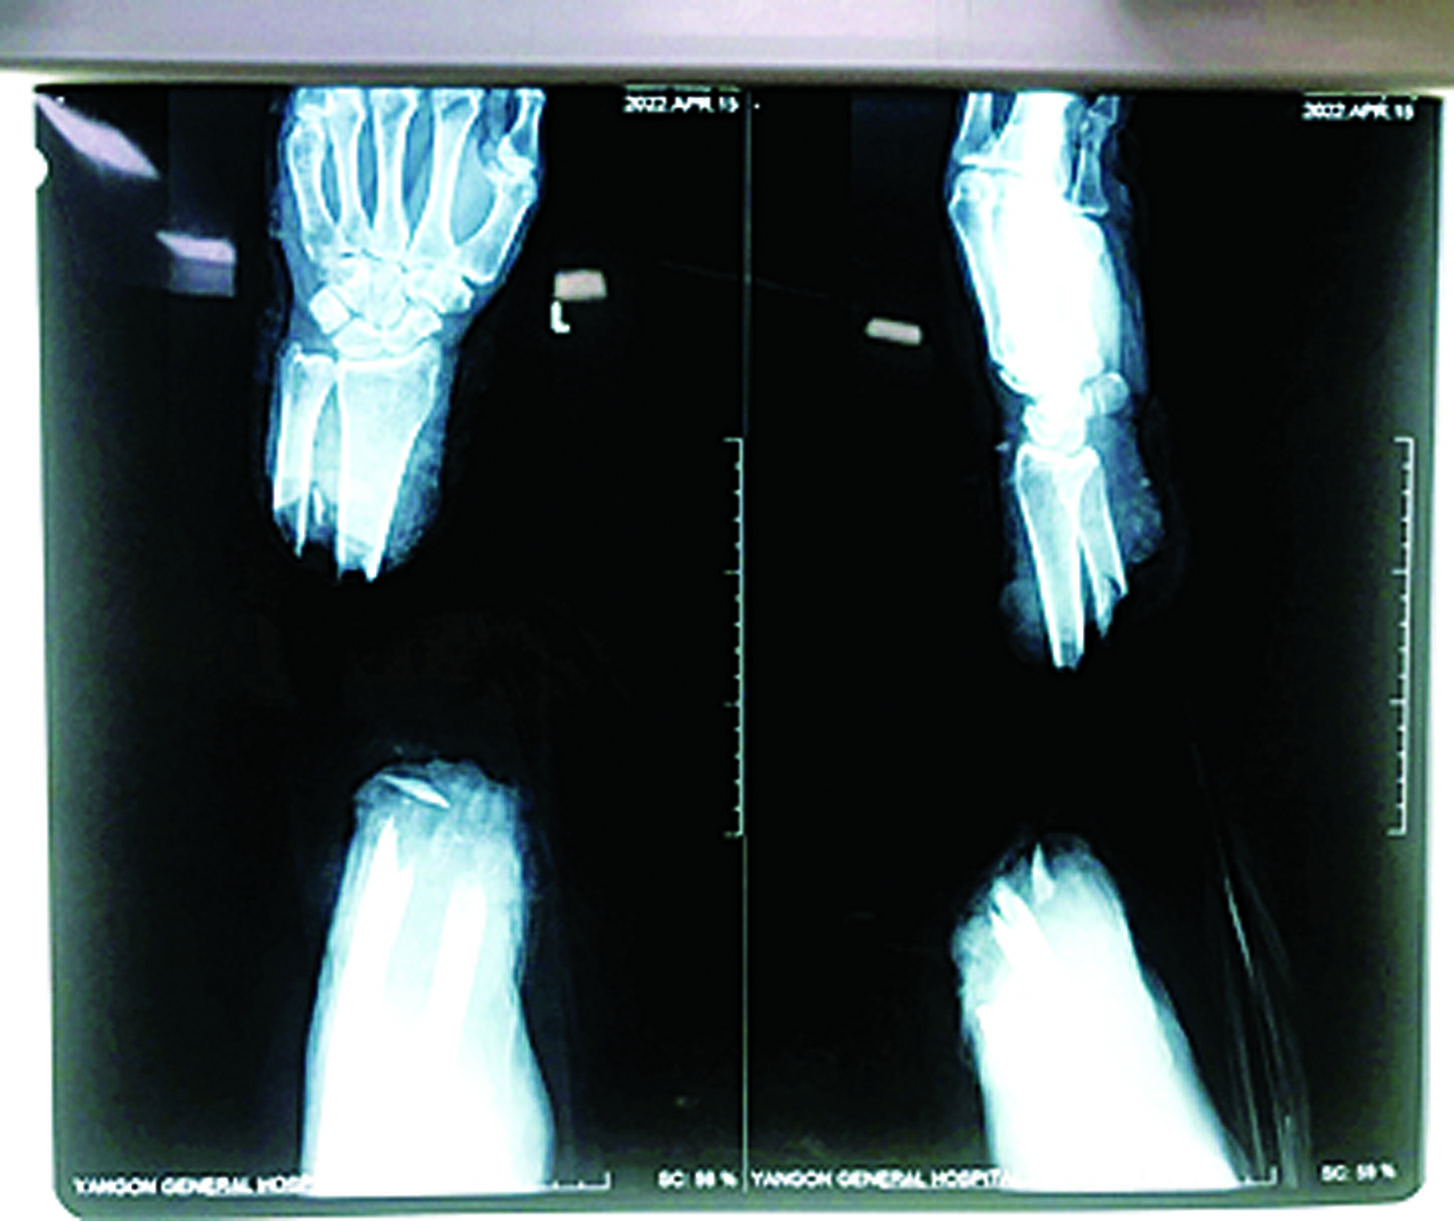

ရန်ကုန်ပြည်သူ့ဆေးရုံကြီး၌ ဧပြီ ၁၄ ရက်တွင် လက်ကောက်ဝတ်အထက်မှ ပြတ်တောက်သွားသော လက်အား ပြန်လည်ဆက်ပေးသည့် ခွဲစိတ်ကုသမှုကို အောင်မြင်စွာ ဆောင်ရွက်ပေးနိုင်ခဲ့ ကြောင်း သိရသည်။

လူနာမှာ ရန်ကုန်တိုင်းဒေသကြီး ကြည့်မြင်တိုင်မြို့နယ်တွင် နေထိုင်သည့် ငါဖမ်းလုပ်ငန်း လုပ်ကိုင်သူဖြစ်ပြီး ဧပြီ ၁၄ ရက် မွန်းလွဲ ၃ နာရီတွင် ဓားဖြင့် ခုတ်ခံရခြင်းကြောင့် ဘယ်ဘက်လက် ၏ လက်ကောက်ဝတ်အထက်မှ ပြတ်တောက်သွားသည့် ဒဏ်ရာ (Amputated Left Forearm) ဖြင့် ရန်ကုန် ပြည်သူ့ဆေးရုံကြီးသို့ အဆိုပါနေ့ ညနေပိုင်းတွင် ပြတ်တောက်သွားသော လက်နှင့် အတူ ရောက်ရှိလာရာ သက်ဆိုင် ရာ ဆရာဝန်များ၊ သူနာပြုများ နှင့် ကျန်းမာရေးဝန်ထမ်းများက လိုအပ်သော အရေးပေါ်ပြုစု ကုသ မှုများ ပြုလုပ်ပေးခြင်း၊ လက်ပိုင်း ဆိုင်ရာခွဲစိတ်ကုသမှု အထူးကု ဆရာဝန်ကြီးများထံ အချိန်နှင့် တစ်ပြေးညီ ဆက်သွယ်ပြီး ပြတ်တောက်သွားသော လက် ပြန်လည် ဆက်နိုင်ရေးအတွက် လိုအပ်သော စမ်းသပ်စစ်ဆေးမှု များ ပြုလုပ်၍ အရေးပေါ် ခွဲစိတ်ခန်းဝင်ရန် ပြင်ဆင်ခဲ့ ကြောင်း။

ခွဲစိတ်ကုသမှုကို ရန်ကုန် ပြည်သူ့ဆေးရုံကြီးမှ လက်ပိုင်း ဆိုင်ရာခွဲစိတ်ကုသမှု ပါရဂူဘွဲ့ သင်တန်းသား ဒေါက်တာ ဖြိုးမောင်မောင် ဦးဆောင်သည့် လက်ထောက် ဆရာဝန်(အရိုး) ဒေါက်တာမောင်မောင်လွင်၊ ဆေး ပညာဘွဲ့လွန် (အရိုး) သင်တန်း သား ဒေါက်တာမင်းသူ၊ ဒေါက်တာ ဟိန်းပြည့်အောင်၊ မေ့ဆေးအထူး ကု ဆရာဝန် ဒေါက်တာထွန်း ထွန်းနိုင်နှင့် အထက်တန်းသူနာပြု ဒေါ်မေသူရတို့ ပါဝင်သောအဖွဲ့က ဧပြီ ၁၄ ရက် ည ၇နာရီ မိနစ် ၅၀ မှ စတင်ဆောင်ရွက်ခဲ့ရာ ဧပြီ ၁၅ ရက် နံနက် ၁ နာရီခွဲတွင် ခွဲစိတ် ကုသမှုပြီးဆုံးခဲ့ကြောင်း သိရ သည်။

အဆိုပါ လူနာ၏ လက်မှာ ခွဲစိတ်ပြီးချိန်မှစတင်၍ သွေးကြော များ ဖြည်းဖြည်းချင်း ပြန်လည် လှည့်ပတ်စီးဆင်းလာပြီး ဧပြီ ၂၅ ရက်မှစတင်၍ အကြောအဆစ် ရောဂါကု ပညာဌာန ပြင်ပလူနာ ဌာနတွင် လေ့ကျင့်ခန်းများ လုပ်ဆောင်ခဲ့ပြီး ဧပြီ ၂၉ ရက်တွင် ဆေးရုံမှ ဆင်းခွင့်ပြုပြီးဖြစ်သည်။